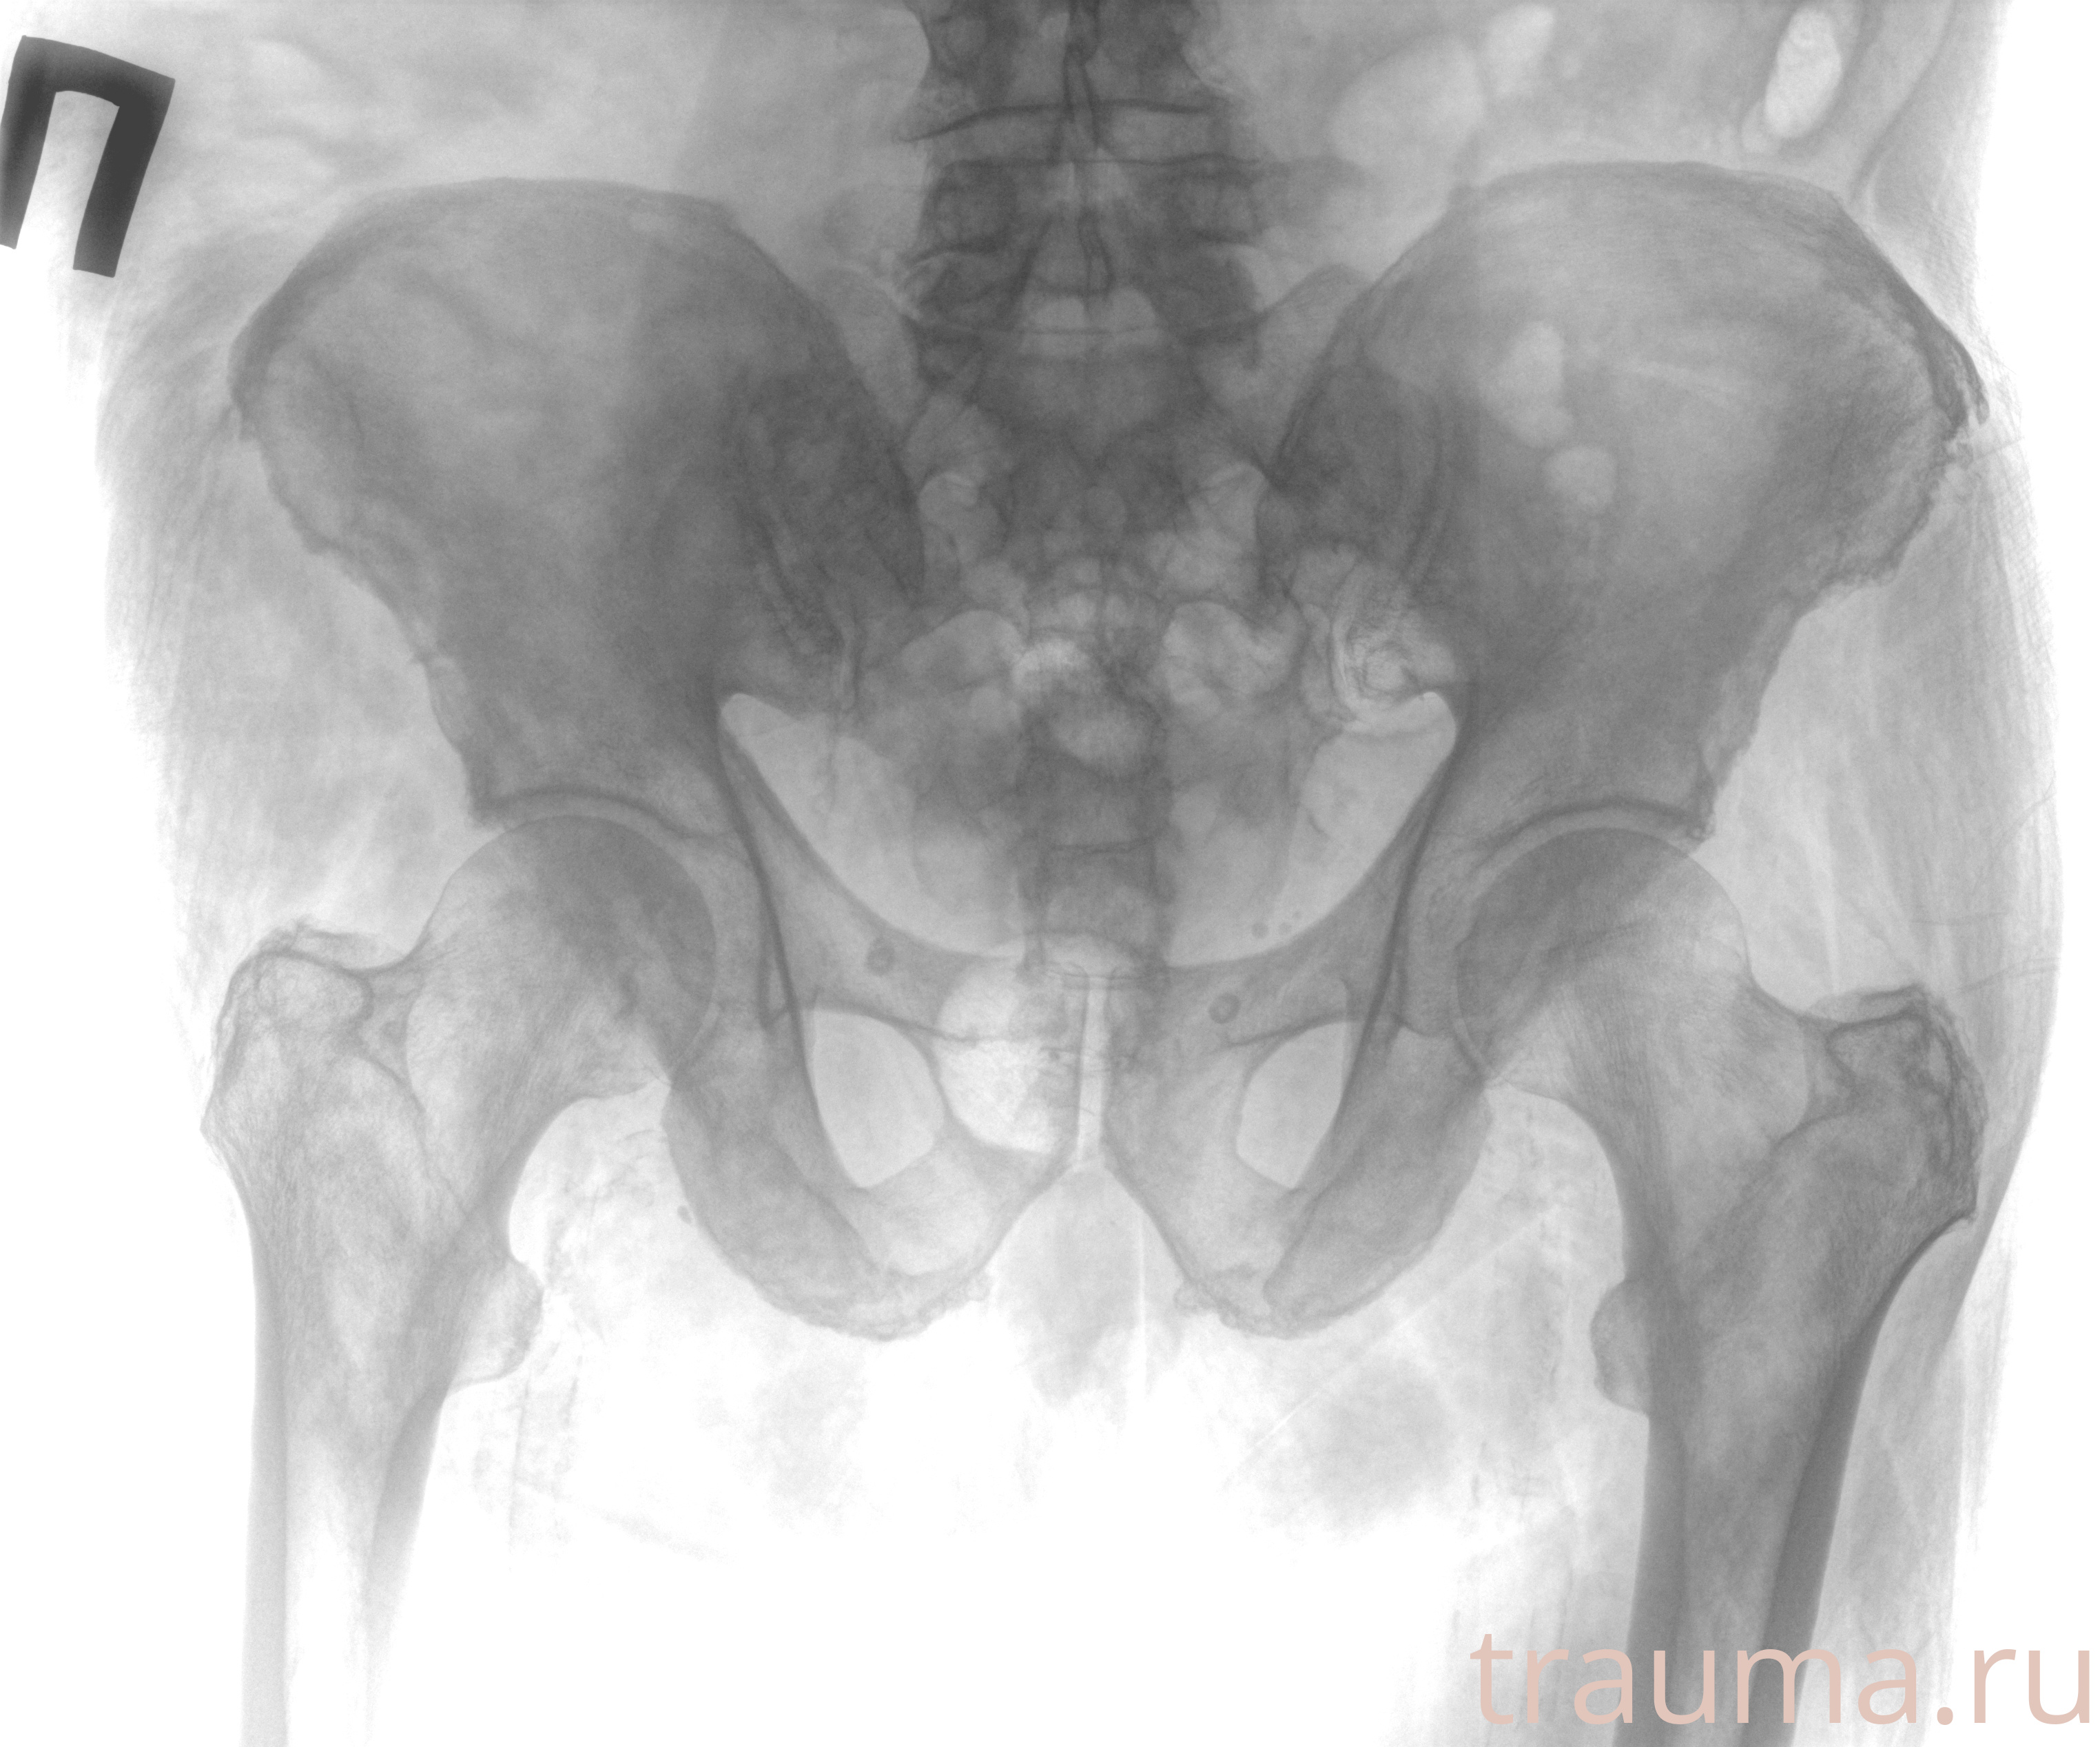

Рентген на дому: по вашему адресу приезжает врач-рентгенолог, травматолог-ортопед с мобильным рентгеновским аппаратом, проводит диагностику травмы или заболевания, делает необходимые рентгенограммы, дает рекомендации по дальнейшему лечению. Получить качественные снимки в домашних условиях возможно благодаря уникальной методике, разработанной МосРентген Центром для института  Склифосовского